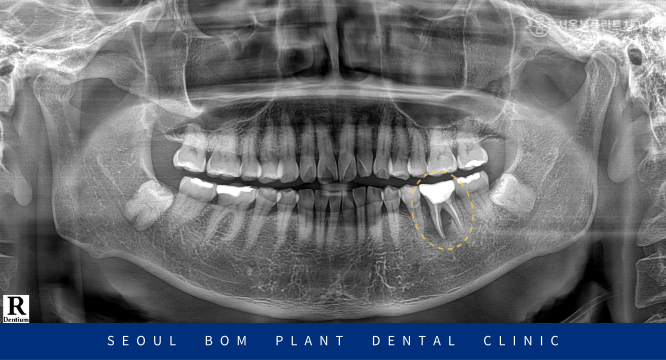

오늘은 아래턱 어금니 통증으로 인해

방이역치과 서울봄플란트치과를

내원해 주신 사례를 소개해 드리겠습니다.

오늘 소개해 드릴 환자분께서는

50대 남성분으로 저작 시

오른쪽 아래턱 어금니 부위의

통증으로 인해 내원해 주셨는데요.

정밀한 검사를 위해

파노라마 촬영을 했습니다.

오른쪽 아래턱 첫 번째 큰 어금니(#36)

주변으로 까맣게 염증이 생긴 것을

확인할 수 있었으며,

뿌리에서도 파절 양상이 보였는데요.

염증의 범위도 컸으며,

치아의 동요도도 있는 상태였습니다.

방치하게 된다면 해당 치아 주변으로

염증이 계속적으로 퍼져 다른 치아에도

영향을 끼칠 수 있기 때문에

발치가 불가피한 상황이었습니다.

해당 치아는 신경치료를 진행한 곳인데

살아있는 신경을 제거하고

치과재료로 충전되어 있습니다.

그동안 감각을 쉽게 느끼지 못해

계속 방치하게 되다가

통증을 느끼기 시작하였을 때는

이미 염증이 심하게 된 케이스인데요.

환자분과 정밀한 상담을 진행한 후

아래턱 왼쪽 첫 번째 큰 어금니(#36)는

발치 후 임플란트를 진행하기로

계획을 수립하였습니다.